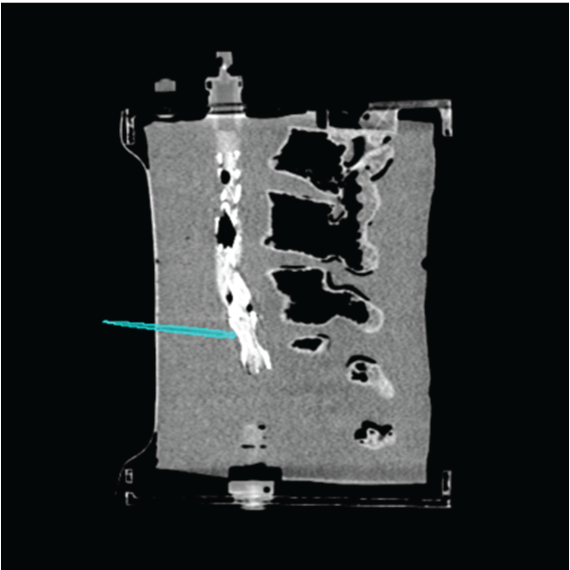

3.4 Phantom experiments

A phantom targeting experiment was conducted to evaluate the accuracy of needle insertion. Fig. 9A shows the experimental setup, including an endoleak phantom, an FG mounting frame, and a Canon Alphenix C-arm (Canon Inc., Tokyo, Japan). Three magnetically tracked needles were inserted into the endoleak phantom. During 2D navigation, the tracked needles (red lines) were projected on the fluoroscopic image, while the actual needles appeared as dark lines. The discrepancies between the two were used to quantify 2D targeting accuracy.

Fig. 9B illustrates the 3D navigation, including 3D reformations, the rendered contrast-enhanced CT volume, and tracked needles. To validate 3D needle insertion accuracy, we acquired a post-insertion non-contrast CT image (Fig. 9C). The inserted needles were clearly visible in three orthogonal views, with the 3D view displaying the inserted needles in silver and the tracked needles in cyan. Needle tip and angle errors were calculated by comparing the tracked needles with their segmented counterparts from the CT image. This process was repeated three times, with a total of nine inserted needles. The overall needle insertion errors were for the tip, and for orientation, as shown in Table 5.